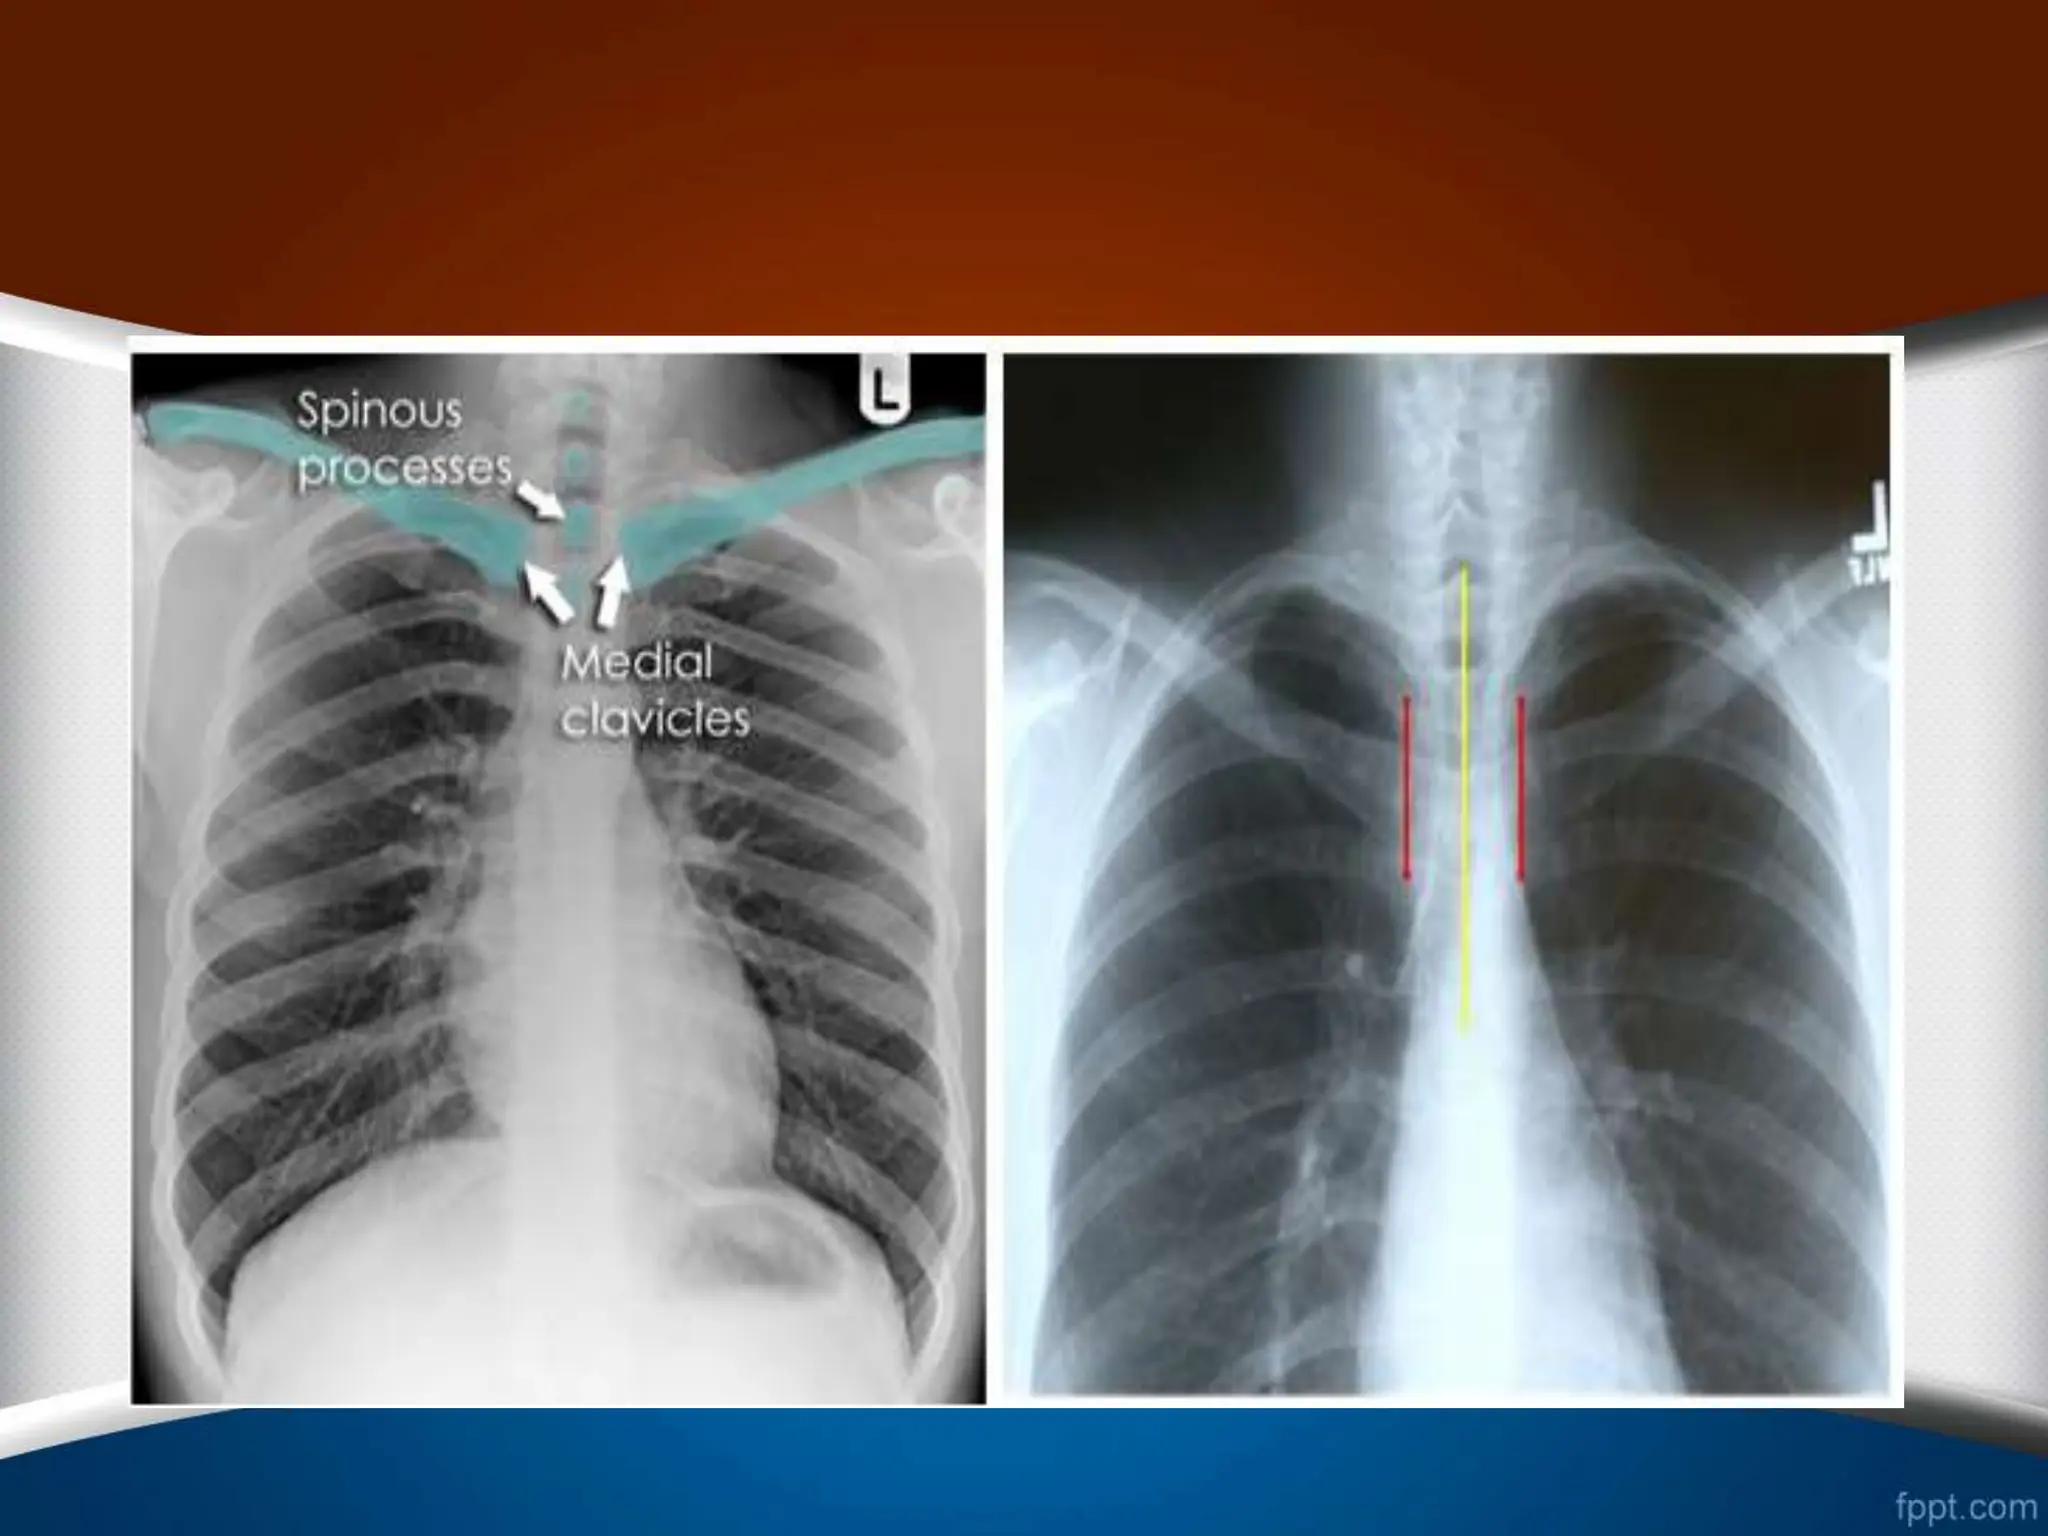

‫چرخش‬ –Rotation

•

‫حاشیه‬ ‫و‬ ‫کند‬ ‫پیدا‬ ‫تغییر‬ ‫قلب‬ ‫کلی‬ ‫شکل‬

‫نامنظم‬ ‫را‬ ‫قلب‬ ‫های‬

‫کند‬

.

(Abnormal configuration)

‫دهد‬ ‫قرار‬ ‫تأثیر‬ ‫تحت‬ ‫را‬ ‫ریه‬ ‫عروقی‬ ‫طرح‬

‫طرح‬ ‫که‬ ‫طور‬ ‫به‬

‫نزدیک‬ ‫اشعه‬ ‫به‬ ‫که‬ ‫سمتی‬ ‫در‬ ‫عروقی‬

‫در‬ ‫و‬ ‫کمتر‬ ‫است‬ ‫تر‬

‫شود‬ ‫دیده‬ ‫بیشتر‬ ‫است‬ ‫دورتر‬ ‫اشعه‬ ‫از‬ ‫که‬ ‫سمتی‬

‫زوایای‬ ‫شدن‬ ‫محو‬ ‫به‬ ‫منجر‬ ‫است‬ ‫ممکن‬ ‫بیمار‬ ‫چرخش‬

‫خانم‬ ‫در‬ ً‫ا‬‫مخصوص‬ ‫کوستوفرنیک‬

‫ها‬

(

‫افزایش‬ ‫خاطر‬ ‫به‬

‫پستان‬ ‫بافت‬ ‫دانسیته‬

)

‫اشتبا‬ ‫به‬ ‫است‬ ‫ممکن‬ ‫که‬ ‫شود‬

‫مطرح‬ ‫ه‬

‫یا‬ ‫و‬ ‫مایع‬ ‫تجمع‬ ‫جمله‬ ‫از‬ ‫پاتولوژی‬ ‫از‬ ‫مواردی‬ ‫شدن‬

‫سازد‬ ‫مطرح‬ ‫را‬ ‫منطقه‬ ‫این‬ ‫فضاگیر‬ ‫ضایعات‬

‫چپ‬ ‫به‬ ‫چرخش‬

.1

‫بزرگتر‬ ‫قلب‬

.2

‫خونتر‬ ‫کم‬ ‫چپ‬ ‫ریه‬ ‫فیلد‬

‫راست‬ ‫به‬ ‫چرخش‬

‫کوچکتر‬ ‫قلب‬

‫خونتر‬ ‫کم‬ ‫راست‬ ‫ریه‬ ‫فیلد‬

‫چپ‬ ‫به‬ ‫چرخش‬ ‫راست‬ ‫به‬ ‫چرخش‬